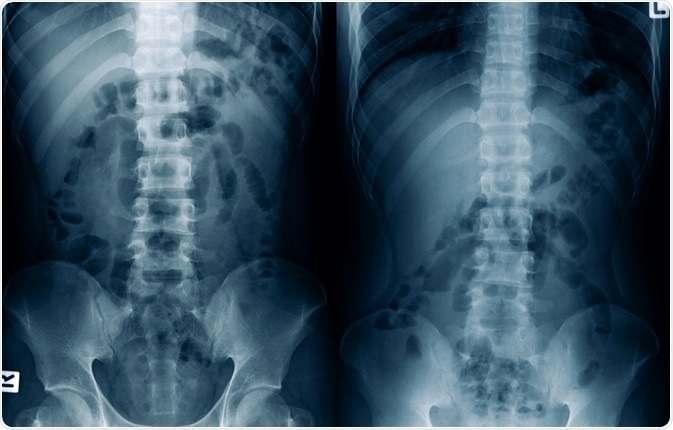

Image Credit: MossStudio / Shutterstock.com

A distinction between postoperative ileus and mechanical small-bowel obstruction is sometimes difficult and confusing. A useful tool for distinguishing these two entities is computerized tomography (CT), although even plain radiography can help establish a correct diagnosis in certain cases.